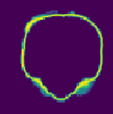

Despite the state-of-the-art performance for medical image segmentation, deep convolutional neural networks (CNNs) have rarely provided uncertainty estimations regarding their segmentation outputs, e.g., model (epistemic) and image-based (aleatoric) uncertainties. In this work, we analyze these different types of uncertainties for CNN-based 2D and 3D medical image segmentation tasks. We additionally propose a test-time augmentation-based aleatoric uncertainty to analyze the effect of different transformations of the input image on the segmentation output. Test-time augmentation has been previously used to improve segmentation accuracy, yet not been formulated in a consistent mathematical framework. Hence, we also propose a theoretical formulation of test-time augmentation, where a distribution of the prediction is estimated by Monte Carlo simulation with prior distributions of parameters in an image acquisition model that involves image transformations and noise. We compare and combine our proposed aleatoric uncertainty with model uncertainty. Experiments with segmentation of fetal brains and brain tumors from 2D and 3D Magnetic Resonance Images (MRI) showed that 1) the test-time augmentation-based aleatoric uncertainty provides a better uncertainty estimation than calculating the test-time dropout-based model uncertainty alone and helps to reduce overconfident incorrect predictions, and 2) our test-time augmentation outperforms a single-prediction baseline and dropout-based multiple predictions.